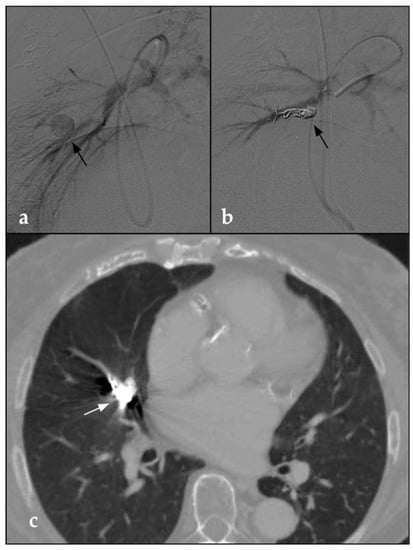

- Piacentino, F.; Fontana, F.; Curti, M.; Imperatori, A.; Venturini, M. Trancatheter Embolization of Pulmonary Artery Pseudoaneurysm with Detachable Coils in Association with Non-Adhesive Liquid Embolizing Agent (Squid): Rare Pulmonary Artery Lesion: Innovative Approach. Acta Biomed. Atenei Parm. 2021, 92, e2021274. [Google Scholar]

- Ierardi, A.M.; Xhepa, G.; Musazzi, A.M.; De Chiara, M.; Beghi, C.; Carrafiello, G. Endovascular Treatment of a Pulmonary Artery Pseudoaneurysm Caused by Swan-Ganz Catheter Deployment in an Anticoagulated Patient. BJR Case Rep. 2015, 1, 20150064. [Google Scholar] [CrossRef]